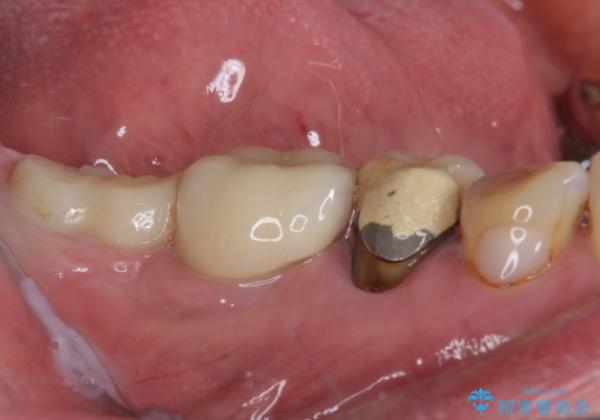

- 強い咬合力により表面のセラミックが剥がれ、裏打ちの金属が見えてしまっていることを気にして来院された患者様です。

仮歯に変えた後、咬合力に耐えることを目的に強化セラミッククラウンにて補綴することとしました。

歯肉が退縮したことで見えていた歯根もセラミッククラウンで覆うことができ、清掃性も改善されました。